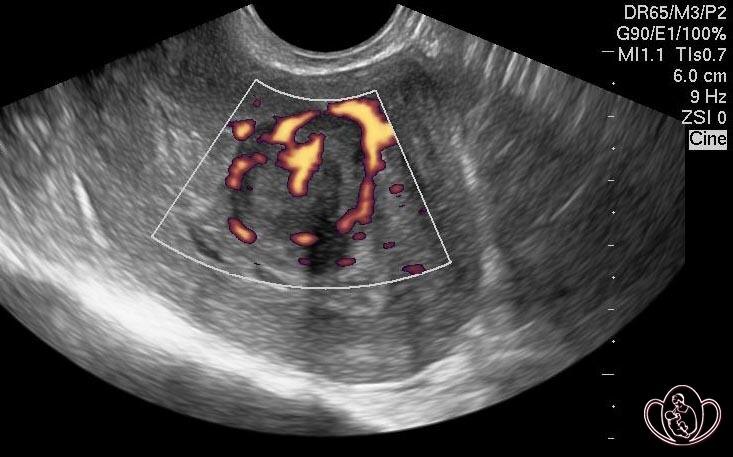

У женщины обильные болезненные месячные со сгустками, анемия (слабость, головокружение), давление на мочевой пузырь. На УЗИ - подслизистая миома, и вместо комплексного лечения ей предлагают понаблюдать или назначают лишь обезболивающие и препараты железа.

Миома растет, деформирует полость матки, нарушает кровоснабжение. Анемия истощает организм. Обезболивающие не решают проблему, а лишь маскируют ее, позволяя болезни прогрессировать до таких размеров, когда щадящее лечение станет невозможным.

Наличие симптомов (кровотечение, боль, нарушение функции соседних органов) — прямое показание к началу активного лечения, а не к наблюдению.